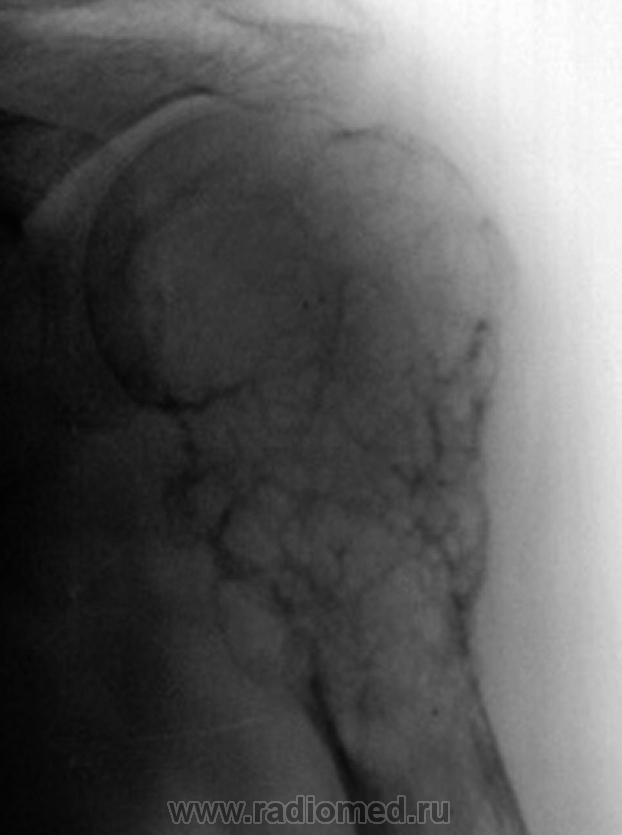

После лечения (аллотрансплантат и металлоостеосинтез).

Совершенно верно - это консервмированный трансплантант (заказ из ЦИТО)представляет собой проксимальную часть плечевой кости.

А эту пациентку прооперировали в мае 2009г.Сейчас находится на химиотерапевтическом лечении,последний снимок выполнен в сентябре,пока все на месте.